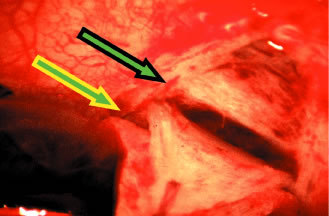

the cornea is covered. The surgical anatomy of the anterior chamber angle in an average eye is shown in Figure 4A and B. Landmarks will differ markedly in eyes that have abnormalities. In the myope, the space between the anterior limbus and the iris root is greater; in the hyperope, it is less. An incision at the corneoscleral sulcus may enter the anterior chamber far anterior to the trabecular meshwork in the myope but may enter the posterior chamber in the hyperope. Because glaucoma in infants is rare, its surgical treatment is not discussed in detail. However, guarded filtration procedure is described later and may be employed with satisfactory results in many patients with congenital glaucoma (trabeculodyspenesis). PREOPERATIVE CARE The reader should refer to the earlier section of this chapter on evaluation of the person. The goal is to move the patient from conditions auguring failure toward those promising success. Obviously, many factors cannot be changed. In the simplest terms, the healthier the eye and the less likely it is that scarring will develop when the eye is injured, the greater the chance for success. Preoperative care is discussed in greater detail in the sections that describe the operative procedures. Many people take aspirin products routinely. Aspirin comes in many forms, and it is part of many compounds. Because it predisposes patients to bleeding, it should be discontinued, if prudent, 2 weeks before surgery. Most people who are taking aspirin are taking it for relatively unimportant indications; some simply may have heard that aspirin can help prevent heart attacks. However, in some patients, aspirin may be an important part of treatment, and discontinuation of the aspirin must be coordinated with the physician who ordered the aspirin. Wherever feasible, it should be discontinued preoperatively. Other agents also predispose patients to bleeding, for example, dipyridamole and anticoagulants, such as dicumarol. These agents should be discontinued an appropriate time before surgery to allow the blood to return to a normal clotting state. Some patients may have to take heparin instead of dicumarol at the time of surgery. This substitution must be individualized and coordinated with the physician managing the patient's anticoagulants. PARACENTESIS A paracentesis should be part of virtually all intraocular glaucoma surgical procedures. This opening in the cornea facilitates management of complications such as bleeding or flat anterior chamber; allows deepening of the anterior chamber at the time of surgery; provides an entry for acetylcholine or sodium hyaluronate; allows the surgeon to determine at the time of surgery how much filtration, if any is occurring through the guarded filtration procedure or sclerostomy; permits safe development of a bleb at the conclusion of surgery; and allows the surgeon to detect whether any tears or leaks are present in the conjunctival flap. The major risk of the procedure is that it may damage the lens. This damage can be avoided by making sure that the instrument used to develop the paracentesis never points toward the lens; holding the instrument parallel to the iris surface eliminates the risk of damaging the lens. Fixation of the globe is critical. The point of fixation should be directly in line with the intended direction of the paracentesis. If the paracentesis is to be made at the 10 o'clock position, extending exactly inferiorly, the sclera should be held directly superior to the 10 o'clock position (Fig. 5). If the surgeon prefers a horizontal paracentesis, starting at the 3 o'clock position, then the globe must be fixated precisely at the 3 o'clock position. An instrument with fine teeth provides good fixation. Examples are the Bonn or Barraquer-Colibri fine-toothed forceps. The tips should be separated only slightly, approximately 1 mm, and then pressed hard against the sclera. Conjunctiva, Tenon's capsule, and episclera are not adequate sites for fixation. We prefer to use a new, sharp, short, disposable 27-gauge needle on a 2- or 5-ml syringe. The needle is held, bevel up, absolutely parallel to the iris surface. In an eye with an iris bombe or a flat anterior chamber, the needle actually may be pointing anteriorly. The tip of the needle is placed against the cornea in the desired position, and the globe is pulled by the fixating hand in the direction opposite to that in which the needle is pointing. For example, if the needle is held horizontally, at the 3 o'clock position of the left eye, then the sclera is grasped at the 3 o'clock position and pulled laterally (temporally) (see Fig. 5). The needle tip enters the cornea. If there is normal or elevated pressure and the chamber is deep, the needle penetrates the cornea after making a paracentesis that is approximately 1 to 2 mm long. If the eye is soft or the chamber is shallow, the needle remains in the cornea and does not penetrate the anterior chamber. This position is desirable in cases in which the cornea is thin, such as in the buphthalmic eye. If the intracorneal track is longer than 2 mm, then the needle and syringe are depressed back toward the apex of the orbit; they are depressed toward the floor of the operating room (see Fig. 5, top right). The tip of the needle must not be angled toward the iris-lens; it must be kept parallel to the iris. As the needle and syringe are pushed toward the floor, the needle changes the curvature of the cornea, permitting it to enter the anterior chamber when advanced. The needle is advanced by a combination of pulling the globe and pushing the syringe. The importance of firm fixation and of introducing the needle against traction provided by the fixation must be stressed. Also, it is essential that the needle not be angled toward the iris, but kept parallel to the iris surface. Once the needle enters the anterior chamber, it is more clearly visible than when it is intracorneal (see Fig. 5, bottom right). The tip is advanced carefully about 1 to 3 mm, until the surgeon is sure that the endothelium has been completely penetrated. The needle is then withdrawn. If the paracentesis has been made with a no. 25 needle, a no. 30 blunt-tipped needle can be introduced later with ease. If the cornea is especially thin or if the surgeon wishes the fit to be especially tight, a 30-gauge needle should be used for the paracentesis. When re-entering the paracentesis track, the blunt needle must be directed exactly parallel to the original track and must hug the posterior (internal, deep) aspect of the track. Often, the neophyte struggles unnecessarily to get the no. 30 blunt-tipped needle into the anterior chamber through a no. 27-size paracentesis. However, when the blunt-tipped 30-gauge needle is angled in the direction of the floor, that is, toward the iris, and slid along the internal aspect of the paracentesis, it enters gracefully. Alternatively, use a sharp 27-gauge needle for the paracentesis and a sharp no. 30 needle for later entry. USE OF SLIP KNOTS AND RELEASABLE SUTURES The use of a slip knot is helpful in achieving the desired level of tightness of the scleral flap in a guarded filtration procedure. Slips knots also have the advantage of being easier to bury than the usual surgeon's knot. They cannot be used to close incisions under tension, but are appropriate for almost all other situations. We use them routinely. Figure 6 illustrates the method of tying slip knots. See p. 24 for a discussion of releasable sutures (Fig. 7). IRIDECTOMY Iridectomy deserves separate treatment in this chapter because, with rare exceptions, its basic purpose is different from that of all other glaucoma surgery. Iridectomy often is performed not to lower IOP but to correct an anatomic aberration, narrowness of the anterior chamber angle (Fig. 8). It is important to explain to the patient why the iridectomy is recommended. Patients usually conclude that glaucoma surgery has as its purpose the lowering of IOP, and unless enlightened to the contrary, most patients anticipate that IOP will be lower after iridectomy. Diagnosis and Classification An extensive description of the diagnosis and classification of the angle-closure glaucomas cannot be given here.1,43 However, the essential component in the diagnosis of the angle-closure glaucomas, gonioscopy, must be mentioned. Differentiation between optical contact and actual adhesion between the iris and the cornea cannot be made without the use of indentation gonioscopy; therefore, the correct diagnosis of the angle-closure glaucomas demands the appropriate use of a gonioscopic lens that can be used in indentation gonioscopy8,44 (Fig. 9). We prefer the Zeiss four-mirror lens on an Unger handle. For the diagnosis of angle-closure glaucoma to be certain, the ophthalmologist must be certain that the symptoms could only be the result of angle closure and that the anterior chamber angle actually has closed. Thus, the search for peripheral anterior synechiae, characteristically between the 10 and 2 o'clock positions of the eye, assumes great significance. Peripheral iridectomy is described in moderate detail because it is our opinion that the general ophthalmologist should still be fully competent in performing a standard surgical iridectomy. Nd:YAG laser iridotomy is clearly the procedure of choice in patients needing an iridotomy. However, it is not always possible. In patients in whom the cornea does not become sufficiently clear to allow a laser iridotomy, an incisional surgical iridectomy becomes necessary. In addition, incisional iridectomy may be necessary in some patients with a diagnosis of pupillary block glaucoma in whom a persistent, patent peripheral iridotomy cannot be achieved with laser techniques. Preoperative Care Most attacks of acute primary angle-closure glaucoma can be treated medically. The longer the attack, the higher the pressure, the more the eye has been damaged, and the less likely the patient is to be harmed by the medications used to treat the attack, the more vigorous the treatment should be. When the attack is brief, the inflammatory signs minimal, and the pressure relatively low, pilocarpine 1% every 5 minutes for four doses often is adequate. Apraclonidine 1% often is helpful in treating patients with high IOP or in cases in which lowering IOP is not expected to be accomplished with the use of pilocarpine alone. When treatment must be maximal, the following routine may be followed: pilocarpine 1% every 5 minutes for four doses; timolol 0.5% immediately and again in 1 hour; apraclonidine 1% immediately; acetazolamide 500 mg intravenously; and an osmotic agent (isosorbide, 30 mg/kg body weight in routine cases; mannitol 20%, 70 ml/kg body weight intravenously in the nauseated patient who can tolerate a large sudden increase in blood volume; or anhydrase glycerol orally, 1 ml/kg body weight in the patient who can take oral medication but is likely to have urinary retention). Topical steroids are appropriate if the eye is inflamed. Occasionally, forceful compression of the anterior chamber with an instrument such as the Zeiss four-mirror gonioprism can push the angle open and help to end the angle-closure attack. Once the attack has been stopped, it is helpful to allow the eye to quiet before proceeding with the iridectomy. Weak pilocarpine administration, such as 1% two or three times a day and aqueous suppressants, such as timolol and acetazolamide, should be continued until the time of surgery. If surgery is indicated on the fellow eye, it may be appropriate to perform an iridectomy on that eye while waiting for the involved eye to quiet. Pilocarpine should be used with caution in both the involved eye and the fellow eye because it can predispose the eye to angle closure by increasing the degree of papillary block or causing the lens-iris diaphragm to move anteriorly. Occasionally, it is impossible to break an attack. In such cases, it is advisable to proceed with surgery promptly, despite the presence of high IOP. Here, a retrobulbar injection of anesthetic agent is appropriate and may help lower the IOP. If unsuccessful, the pressure will be brought down easily by paracentesis at the time of surgery. When a peripheral iridectomy is performed, the pupil should be as small as possible. The use of mild pilocarpine is an easy, effective approach. In cases in which the IOP remains elevated or the sphincter is nonfunctional, however, reducing the size of the pupil may be difficult. Multiple instillations of pilocarpine are not recommended in such cases. Usually, they only make the patient systemically ill and the eye inflamed; they do not reduce the size of the pupil. If the sphincter is functional, the pupil will contract quickly once the IOP has been lowered. On the other hand, if the surgeon is planning to perform a sector iridectomy, it is best to have the pupil dilated as widely as possible. Such a sector iridectomy probably is the preferred procedure in patients with severe iris atrophy, a dilated fixed pupil, or a cataract that is limited to the visual axis. Operative Technique Adequate anesthesia for surgical iridectomy performed with a blade is provided by topical administration of an agent such as proparacaine 0.5% eye drops. Tetracaine also is effective, but it appears to have a slightly more irritating effect on the corneal epithelium. Proparacaine 0.5% given approximately every 30 seconds for ten doses 10 minutes before the procedure and then followed by about five instillations after the eye has been prepared and draped, immediately before the surgery, almost always gives satisfactory anesthesia. It is even possible to place a superior rectus bridal suture without causing undue discomfort. In most cases, it is preferable to perform a facial nerve block with a modified O'Brien block.45 This approach allows easier and more comfortable placement and retention of the speculum. Because the procedure usually lasts only about 5 to 15 minutes, a short-acting injection anesthetic, such as lidocaine, is appropriate. The relevant anatomic considerations are shown in Figure 4A and B. The operative technique is shown in Figure 10. The iridectomy should be performed so that the only instruments that enter the anterior chamber are the needle that is used to develop a paracentesis track and the tip of the blade that is used to make the corneoscleral incision. The advantages of the paracentesis so greatly outweigh the minute risks associated with it that we believe that it should be performed routinely. The technique is described in detail earlier in this chapter and is illustrated in Figure 5. When properly performed, this procedure is virtually without risk, even in patients with extremely shallow or flat anterior chambers. Without such an opening into the anterior chamber, the integrity of the incision cannot be tested, blood in the anterior chamber cannot easily be irrigated away, and chamber deepening cannot readily be performed. To prevent the tip of the knife used to develop the corneoscleral incision from damaging the iris or lens, it is preferable to use a broad blade, such as the no. 67 Beaver blade. Multiple small scratches are made, with the surgeon verifying that the depth of the incision is uniform from end to end. Some surgeons prefer an anteriorly shelved incision because it tends to close more easily; in the past, many surgeons did not place a suture through this type of incision. However, a perpendicular incision allows the iris to prolapse more readily, gives better visualization, and facilitates the procedure. The availability of fine suture material allows tight closure of the incision with minimal irritation or difficulty. The scissors used to perform the iridectomy should be sharp and should be tested immediately before the procedure to ensure their proper operating condition. We prefer the use of a preplaced suture, as seen in Figure 10. This approach provides a clearer view of the process of creating the corneal incision, it aids in prolapsing the iris, and it allows for immediate closure with a suture that the surgeon knows is perfectly placed. Any of a number of sutures is satisfactory. Absorbable polyglactin [Vicryl (Ethicon, Somerville, NJ)] works well and has the advantage of not requiring removal. A 9-0 nylon suture also is satisfactory; it is thick enough to be used to retract the tissue yet fine enough to be well tolerated. The small fornix-based flap can be closed by stretching it toward one side, especially if a radial relaxing incision approximately 2 mm long and extending from the limbus has been performed (Fig. 11). This closure can be done with the same suture used to close the corneoscleral incision, or it can be coapted with the wet-field cautery. If the scissors performing the iridectomy are held as shown in Figure 12 the iridectomy will tend to be broad based but will remain basal, reducing the chance that the patient will have a disturbing sense of double vision postoperatively. It is important to stress that in a properly performed iridectomy, it is not necessary to insert the iridectomy forceps into the anterior chamber. To do so unjustifiably increases the risk of damage to the cornea, lens, and zonules. If a fine-toothed forceps such as a Bonn forceps is employed, the surgeon must be careful to pull the iris out of the anterior chamber far enough to ensure that the iridectomy will he penetrating. A nontoothed forceps, such as a McPherson tying forceps, offers the relative advantage of providing a less secure grip on the iris, requiring the surgeon to grasp more tissue. The disadvantage, however, is that control of the tissue is less certain, and the forceps must be inserted further into the incision.